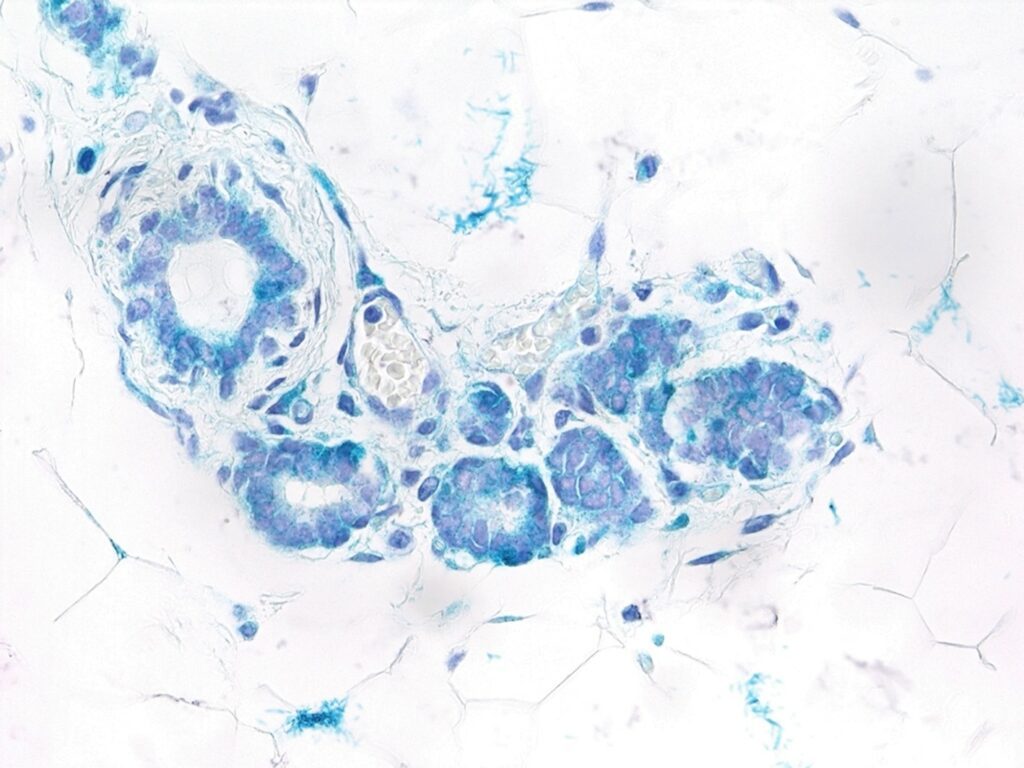

En aquesta seqüència d’esdeveniments en què RANK està activat, l’equip ha observat que en les fases més primerenques de la malaltia, la senescència s’activava fonamentalment en les cèl·lules luminals de l’epiteli mamari, aquelles que estan més exposades a la llum dels conductes mamaris.

En el treball suggereixen que aquestes cèl·lules senescents, no tumorals, alliberen una sèrie de substàncies que actuen de forma paracrina -a distància sobre les cèl·lules veïnes- sobre cèl·lules luminals i basals, aquestes últimes allunyades de la llum dels conductes. En resposta a aquest estímul, les cèl·lules luminals i basals adquireixen característiques de cèl·lules mare, i tot i l’enganyós retard inicial, els tumors resultants són més agressius, creixen ràpidament, generant metàstasi en pulmó.